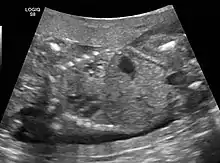

CPAMs are often identified during routine prenatal ultrasonography. Identifying characteristics on the sonogram include: an echogenic (bright) mass appearing in the chest of the fetus, displacement of the heart from its normal position, a flat or everted (pushed downward) diaphragm, or the absence of visible lung tissue.

Congenital pulmonary airway malformation in a fetus, ultrasound at 19 weeks -sagittal. Stomach top right of image, heart displaced to bottom left of image (anatomically on the right side of fetus.)

The earliest point at which a CPAM can be detected is by prenatal ultrasound. The classic description is of an echogenic lung mass that gradually disappears over subsequent ultrasounds. The disappearance is due to the malformation becoming filled with fluid over the course of the gestation, allowing the ultrasound waves to penetrate it more easily and rendering it invisible on sonographic imaging. When a CPAM is rapidly growing, either solid or with a dominant cyst, they have a higher incidence of developing venous outflow obstruction, cardiac failure and ultimately hydrops fetalis. If hydrops is not present, the fetus has a 95% chance of survival. When hydrops is present, risk of fetal demise is much greater without in utero surgery to correct the pathophysiology. The greatest period of growth is during the end of the second trimester, between 20–26 weeks.